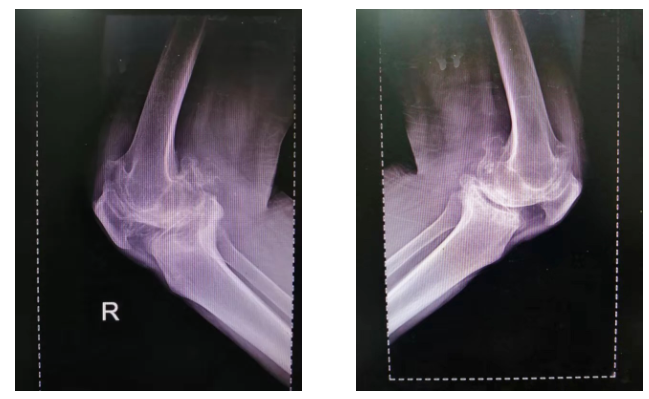

患 者:男,68岁。

主 诉:双膝渐进性加重的疼痛伴畸形10余年。

查 体:左膝活动范围20°~35°,HSS评分25分;右膝活动范围10°~30°,HSS评分20分。

检 查:术前负重位X-ray显示双膝重度骨性关节炎合并屈曲内翻畸形。

术前影像:

术前正位

术前侧位